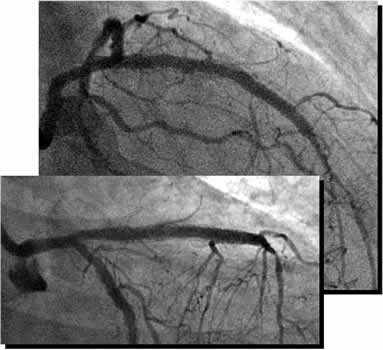

| Diagnosis: OMI (A), AP, SVD

Present Illness: '97.9 AMI (A) '00.11~ AP '00.12.13 Stenting for LCX '01.1.24 Stenting for #6 PCI for #7 CTO (unsuccess) '01.5.9 POBA+stenting for #6 distal |

| Coronary Risk Factor: DM |

| Final CAG Findings:'01.9.5 LVG: asynergy (A), EF: 71% CAG: #6 90% (ISR) #7 CTO (collateral from RCA) |